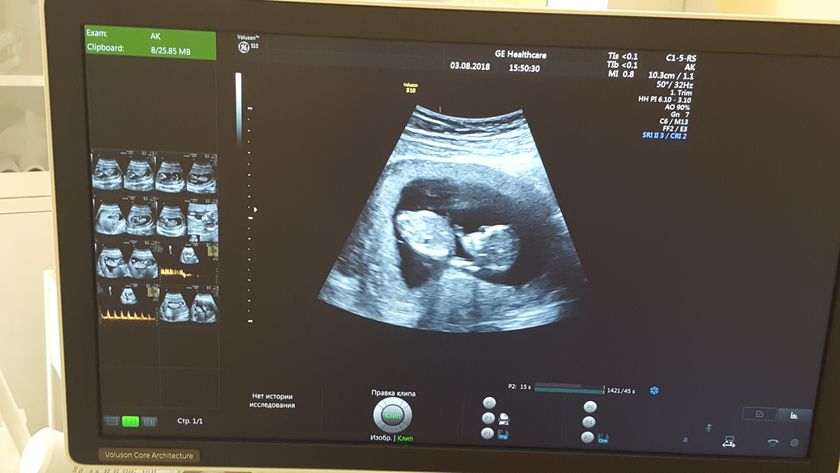

Всем привет!) Была я вчера на своем первом скрининге в клинико-диогнастическом центре им. Виноградова у врача Тимм Людмилы Леонидовны. Прием у меня был 15:20, но приняли меня только в 15:45. Небольшое скопление людей было, но это не страшно. По сути у кого-то узи может занять 10 минут, у кого-то все 40 в зависимости от того, как лежит малыш. До этого я была на скрининге 26 июля, но меня перезаписали, т.к. ктр был 43 мм, а принимали с 45 мм. Людмила Леонидовна дважды пропускала мужа посмотреть на малыша, чему я была безумно рада) Ещё вчера я первый раз послушала сердечко малыша ? Чсс 168 ударов) Фото не дают, разрешают фотографировать и снимать видео, но я конечно же промахнулась))) и не смогла снять ?? носик визуализируется, малыш активно помахал нам своей маленькой ручкой) В общем всё что было озвучено — " ничего плохо я вам не скажу, подробнее через неделю у врача") Всё-таки вчера поставила мне ровно 13 недель, как и есть на самом деле) Я верю, что всё с нашим малышом отлично ??? чего желаю и всем вам)